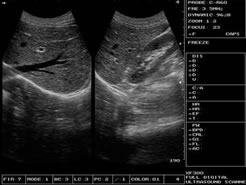

八段TGC精準分段、總增益調(diào)節(jié)

> 八段TGC總增益調(diào)節(jié),中英文自由切換

增益控制:8段TGC、GAIN調(diào)節(jié),總增益連續(xù)可調(diào);